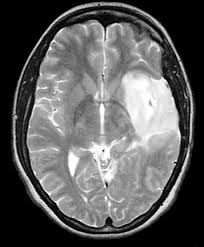

A major determinant of cell fate is regulation of cell cycle. Tight regulation of this process is lost during the course of development and progression of various tumors. The ubiquitin-proteasome system (UPS) constitutes a universal protein degradation pathway, essential for the consistent recycling of a plethora of proteins with distinct structural and functional roles within the cell, including cell cycle regulation. High grade tumors, such as glioblastomas have an inherent potential of escaping cell cycle control mechanisms and are often refractory to conventional treatment. Here, we review the association of UPS with several UPS-targeted proteins and pathways involved in regulation of the cell cycle in malignant gliomas, and discuss the potential role of UPS inhibitors in reinstitution of cell cycle control.